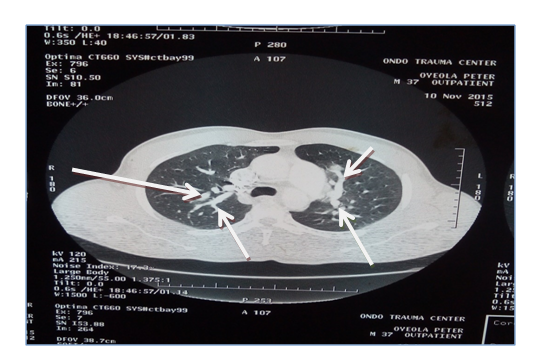

The results of laboratory investigation revealed packed cell volume (38%). Other cells counts were within normal limit but for the peripheral blood film that showed microcytes, macrocytes and anisocytosis. Chest radiograph showed widespread rounded opacities in both lung fields while constrast enhanced CT scan revealed bilateral multiple saccular dilatations of the pulmonary arterials in keeping. Sputum for acid and alcohol fast bacilli and Gene expert (negative), erthrocyte sedimentation rate (40mm/hr), Hepatitis screening (HBsAg, Anti-HCV were both negative), HIV rapid serology test (negative), and VDRL for Syphilis (negative). The values of Anti-Nuclear Antibody, pANCA, cANCA were within normal limit and pathergy test was negative after 48hrs.

Figure 2 Chest X-ray: arrows show rounded opacities seen in both lung fields.

Figure 3 Shows a contrast enhanced Chest CT of patient that revealed bilateral multiple saccular dilatations of the pulmonary arterial branches